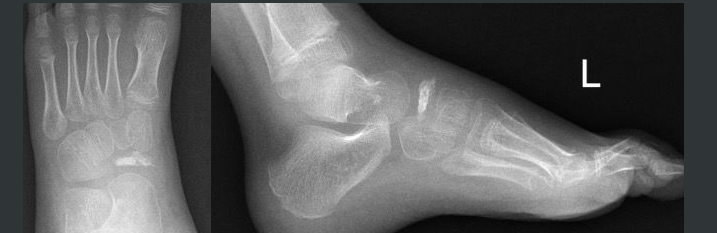

Maladie de Kohler

- Ostéonécrose du Naviculaire